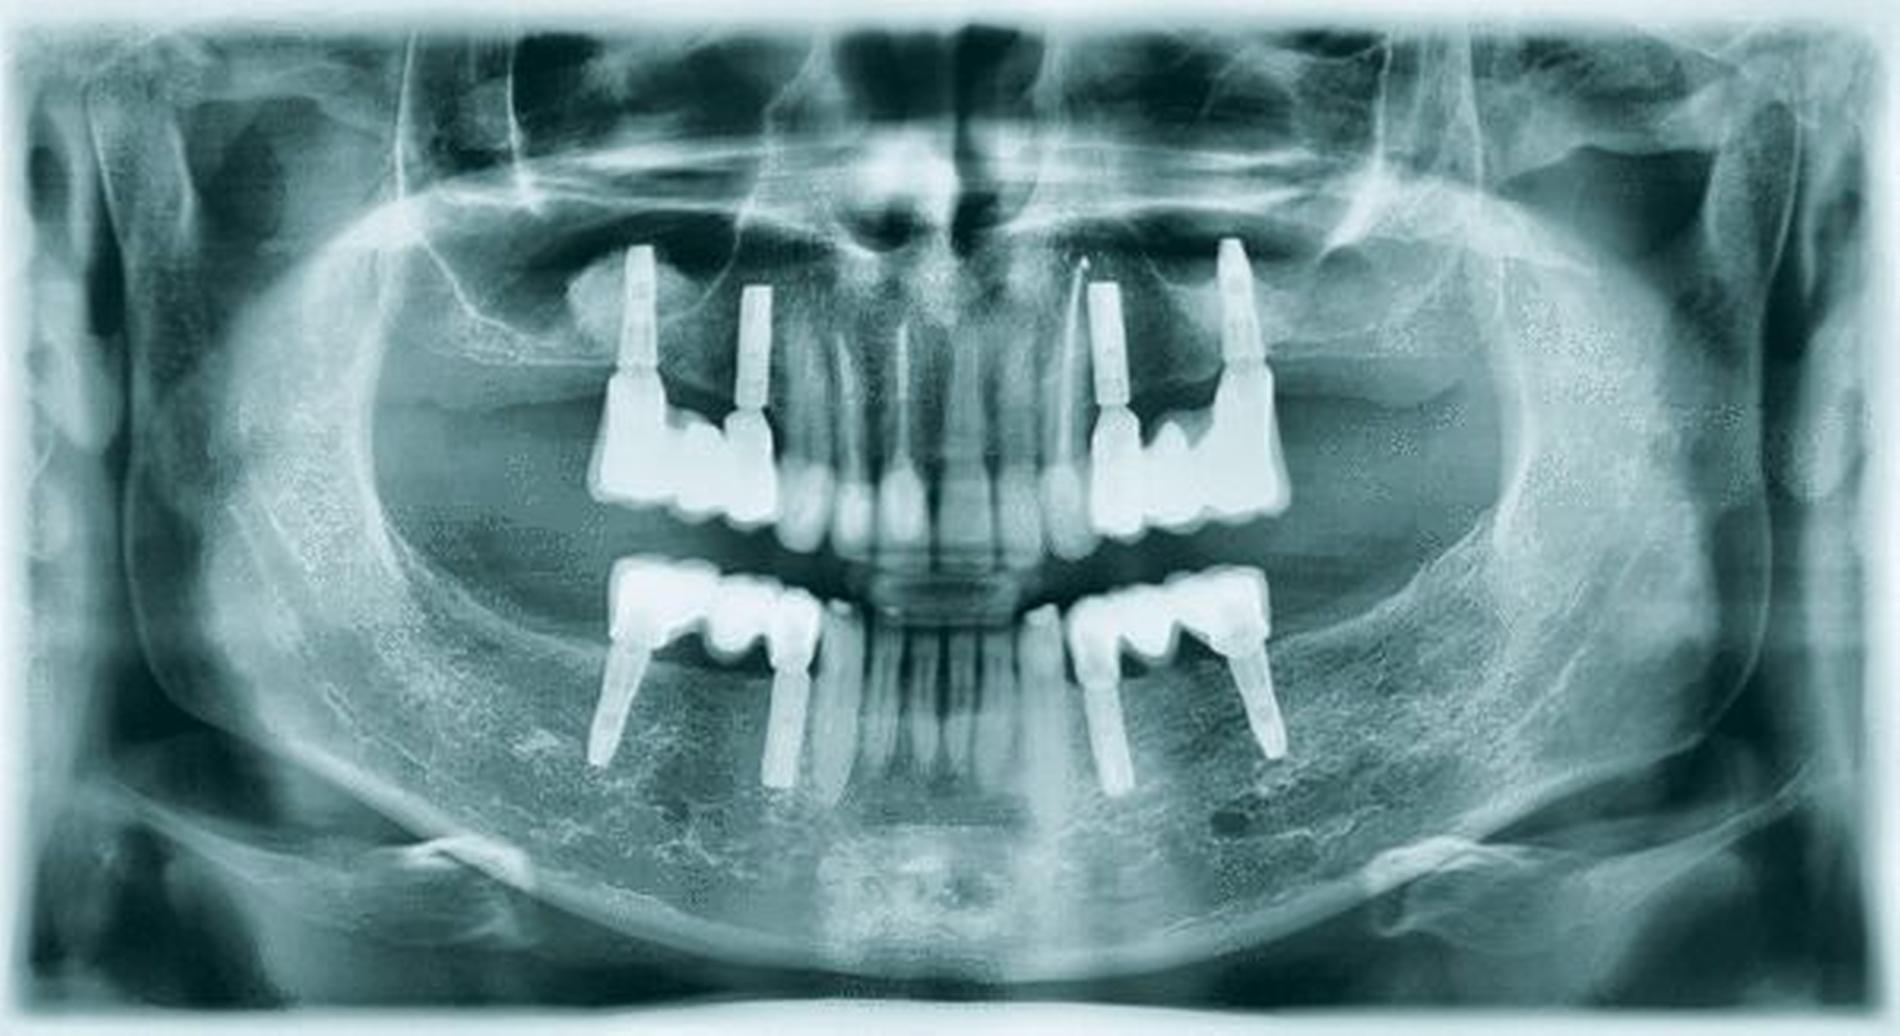

Dem Beginn der zu diesem Zeitpunkt erforderlichen Therapie war eine achtjährige Zahnarztabstinenz und eine damit einhergehende starke Vernachlässigung der Mundhygiene vorausgegangen (Abbildungen 1a-c). Als Grund für die lange Zahnarztabstinenz gab der Patient eine Zahnarztphobie an. Sein äußeres Erscheinungsbild war durchaus gepflegt und stand somit nicht im Einklang mit der oralen Situation. Eine Begründung, warum es zu dem offensichtlich desaströsen Zustand seiner Bezahnung gekommen war, konnte oder wollte der Patient nicht äußern. Die Reaktionen waren auf Nachfrage eher ausweichend und nichtssagend. Der Patient kann als gut situiert bezeichnet werden. Er trat eher introvertiert auf und verbarg seine Zähne beim Reden durch die Lippe.

Der allgemeinzahnmedizinische Befund zeigte ein generalisiert-kariöses Gebiss mit vollständig zerstörten Zähnen im Seitenzahnbereich (Abbildungen 1a-c). Die Zähne 13, 21, 22, 33–43 reagierten beim CO2-Sensibilitätstest positiv. Die restlichen Zähne im Ober- und Unterkiefer zeigten bei Vitalitätsprüfung keine Reaktion. Die Sondierungstiefen lagen im Frontzahngebiet von Ober- und Unterkiefer bei 3–4 mm sowie im Seitenzahnbereich bei größer/gleich 5 mm. Die Ober- und Unterkieferfrontzähne wiesen – im Gegensatz zum Seitenzahnbereich – keine erhöhten Lockerungsgrade auf.

Das OPG (Abbildung 2) zeigte kariöse Defekte an allen Zahnkronen sowie periapikale Osteolysen von 18–15, 24–28, 38–34 und 44–48. Die Zähne 13–23 wiesen kariöse Defekte mit Beteiligung der Pulpa auf. An den Unterkieferfrontzähnen waren keine größeren Defekte oder apikale Aufhellungen zu erkennen.